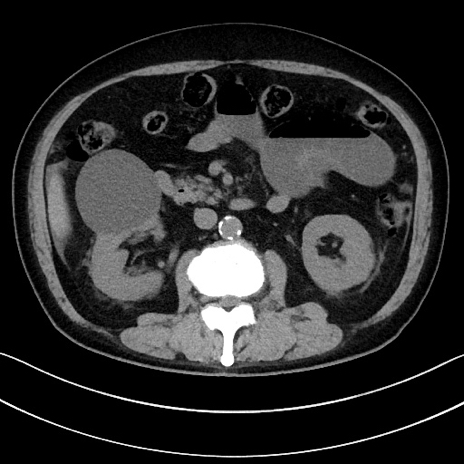

症例15(横断像)

【症例】70歳代男性

【主訴】腹痛

【現病歴】今朝から腹痛あり。全体的に痛い。特に左上の方。排ガスが今日はない。冷や汗が出る。

【既往歴】直腸癌術後

【身体所見】左側腹部〜上腹部に圧痛あり。腹膜刺激症状明らかなではない。軽度反跳痛。左下腹部に術後瘢痕あり。

【データ】WBC 7700、CRP 0.02